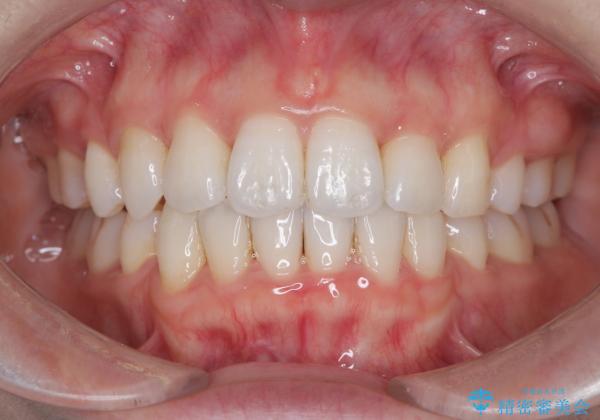

【抜歯インビザ】凸凹を綺麗になおしたい

- 前歯の凸凹を主訴に来院されました。

叢生量が多いため、抜歯が必要となるため、ワイヤー矯正をお勧めしましたが、患者さんの希望によりインビザラインで治療を開始しました。途中でワイヤーリカバリーを必要とせず終了でき患者さんには満足していただけました。